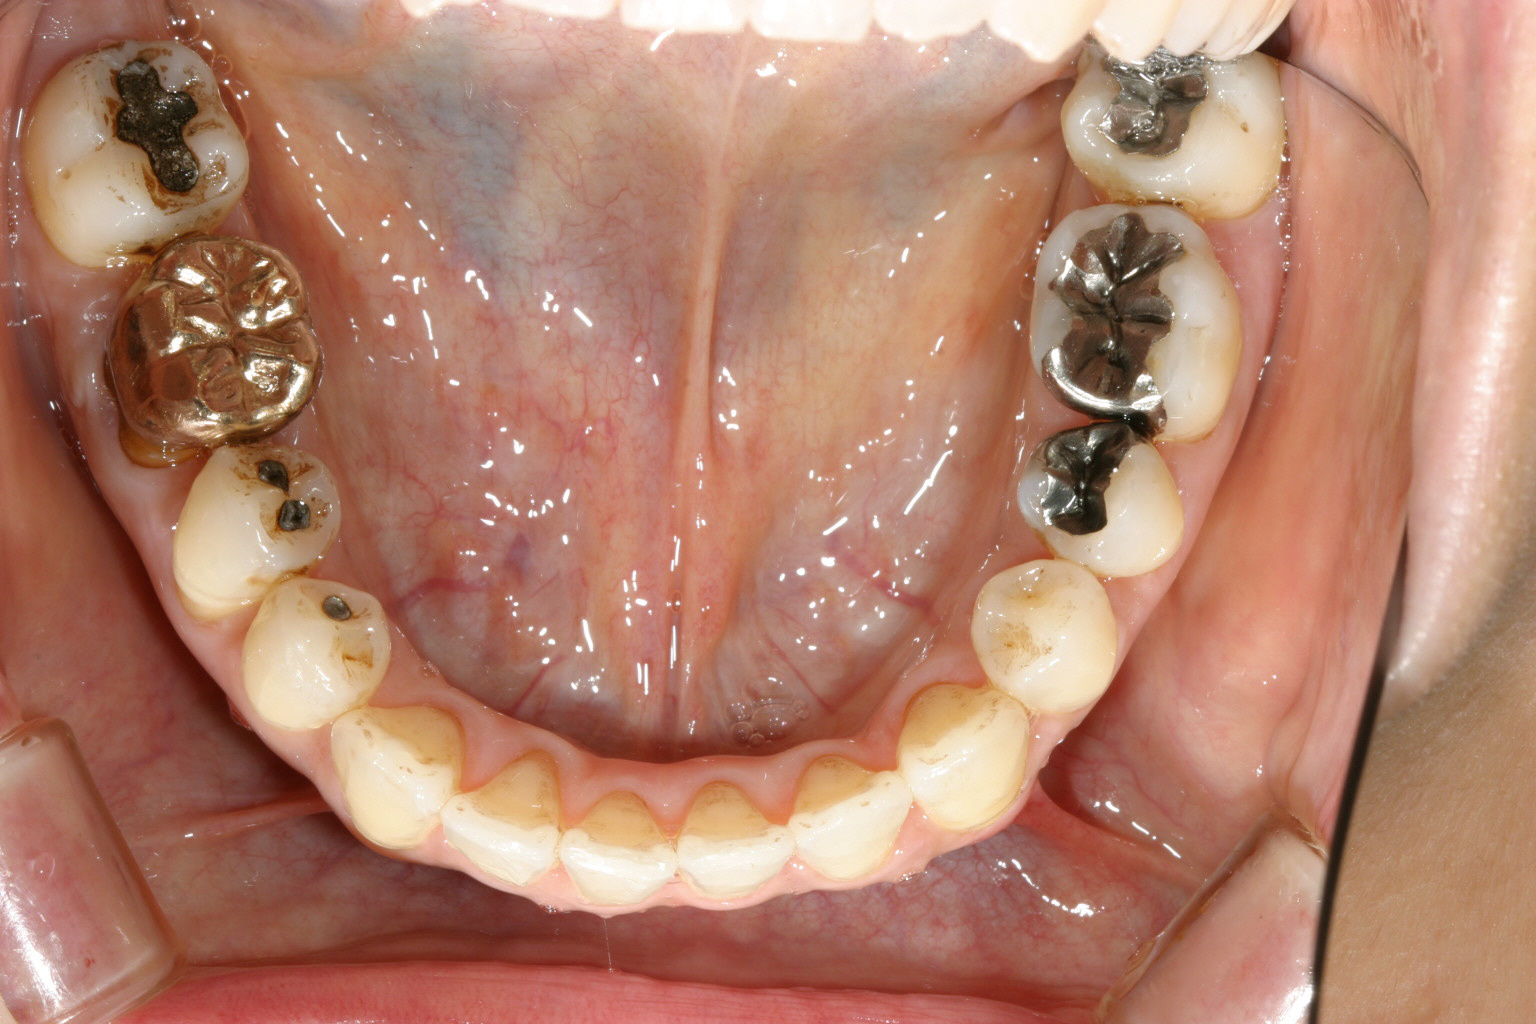

下顎も補綴物が多く又前歯部にガタガタが見受けられます。